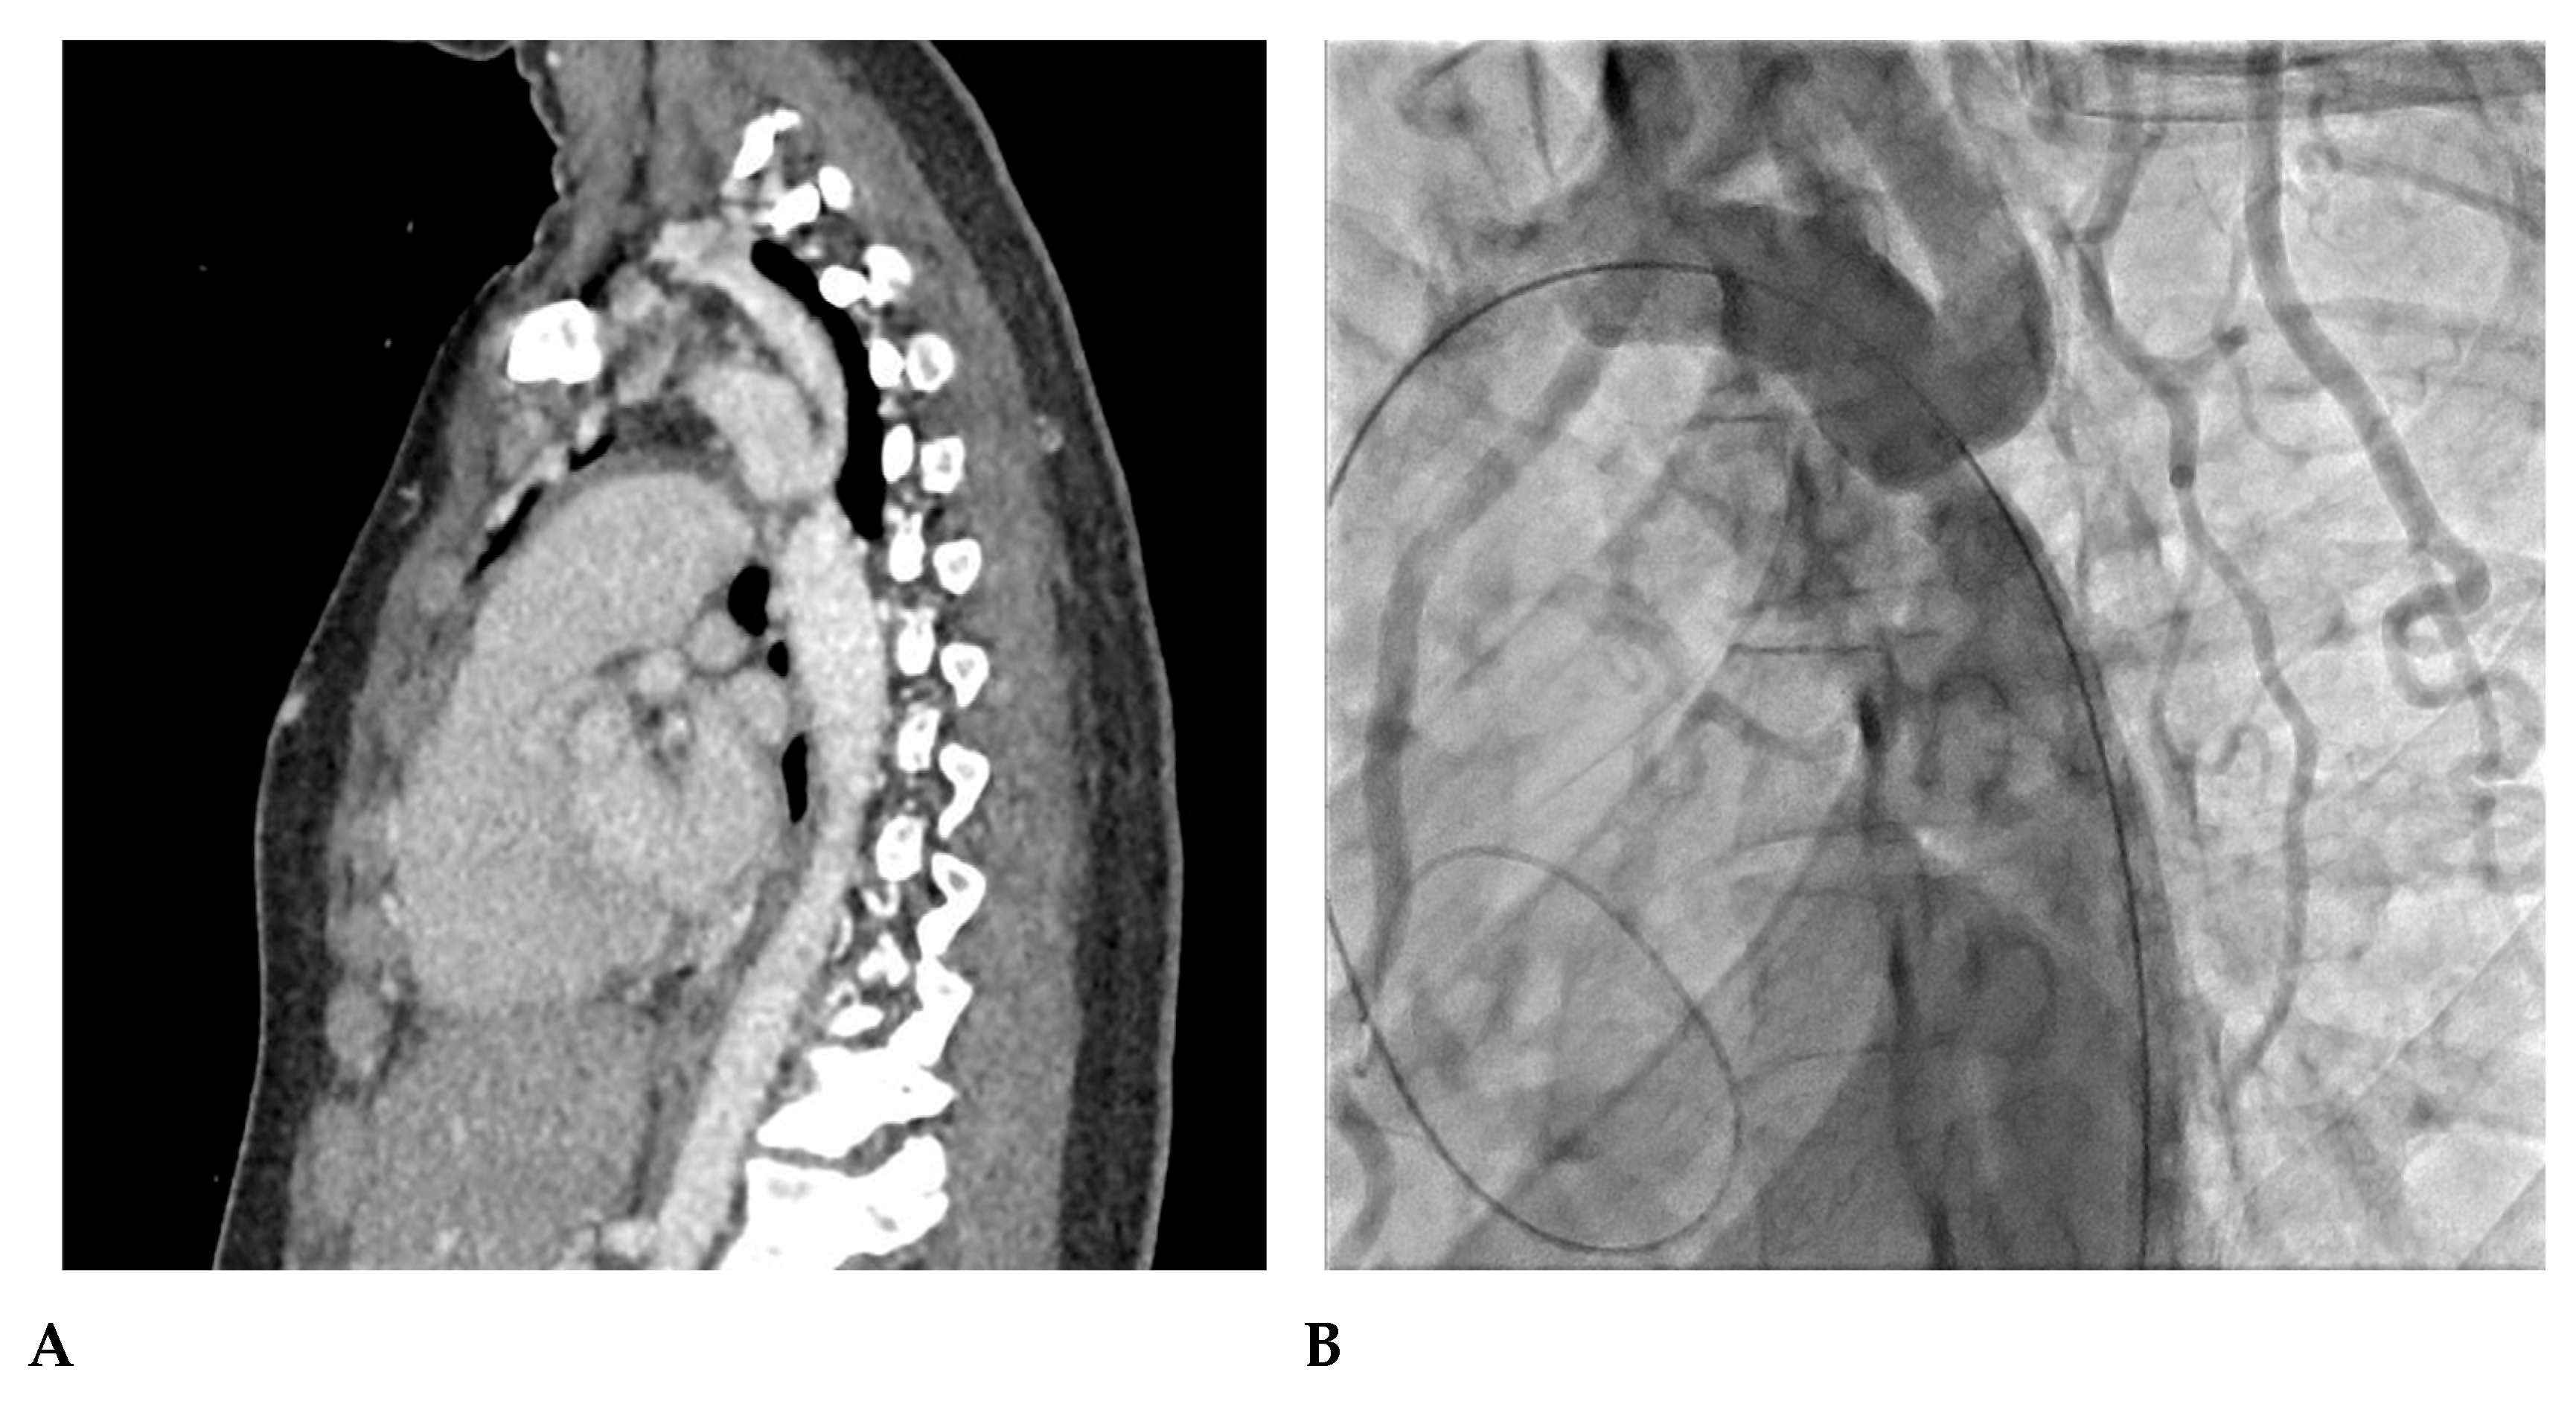

7. Our Experience-Case Series